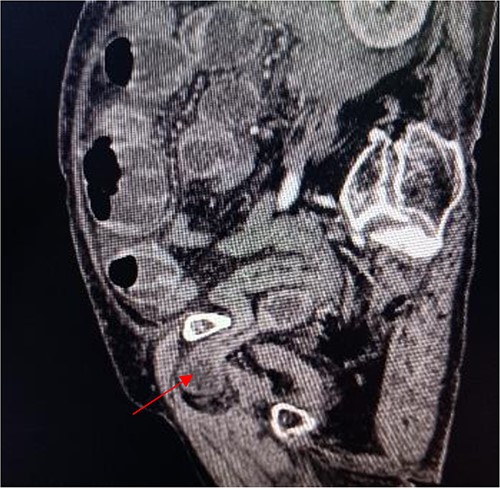

Computed tomography axis map showing the small intestine entering the femoral triangle (red arrow).

An 86-year-old female complained of constipation with abdominal pain, nausea, and vomiting for ˃2 weeks. The patient had defecated once, after conservative treatment with an enema in a local hospital, with less abdominal pain and no nausea or vomiting; hence, she was admitted to our hospital for further diagnosis and treatment. The patient’s body temperature was 36.8°C, pulse rate was 87 beats/min, respiration rate was 18 breaths/min, and blood pressure was 125/76 mmHg. The patient was conscious and had a thin appearance, and physical examination indicated that the abdomen was soft, and without tenderness and rebound pain. Routine blood examination showed that hemoglobin was 87 g/L and hematocrit was 28.3%. Abdominal computed tomography revealed the right lower abdominal small intestine protruding into the femoral triangle through the obturator; the upstream intestine was distended and expanded, and multiple fluid levels were observed in the intestinal lumen. Multiple lymph nodes were noticed in the abdomen and retroperitoneum; the large ones had a diameter of ~1 cm. Uneven thickening and enhancement of the local ascending colon were noted.